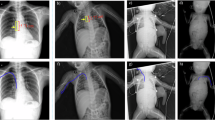

Nonelective PICC removal occurred in 28.4% and complications in 34.4% of infants. Nonelective removal (p < 0.001) and complications (p = 0.006) occurred more often with upper than lower extremity PICCs. Malposition in the first 72 h (p = 0.0009) and over time (p = 0.0003) were more common in upper extremity PICCS; however, upper extremity PICCs were associated with a decreased incidence of phlebitis, edema, and perfusion changes (p = 0.03).